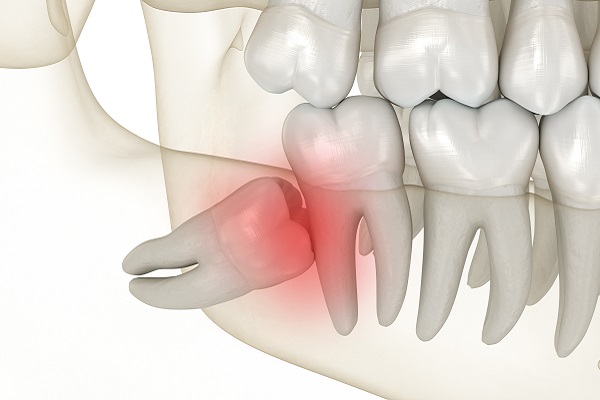

매복사랑니 예시

사진 왼쪽아래(실제 오른쪽 아래) 사랑니가 묻혀있어 옆 치아를 밀고 있으며, 신경관에 닿아있을 것으로 추정되는 사랑니

예를 들어 위 이미지대로 사랑니가 자라면서 옆에 있는 어금니를 계속해서 밀어내는 경우라든지,

사랑니가 잇몸 위로 올라와서 옆에 있는 어금니와의 사이에 음식물이 자주 낀다든지 하는 경우에는 발치를 해주시는 것이 좋습니다.

이런 경우에는 사랑니를 발치하지 않을 경우 옆에 있는 어금니까지 함께 썩거나 염증이 퍼지는 악영향을 미칠 수 있기 때문에